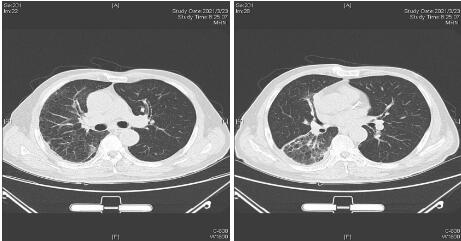

1 资料与方法男性,62岁,因“咳嗽咳痰伴发热5 d,气促2 d”于2021年1月26日就诊本科。1月21日患者淋雨后出现咳嗽咳痰,咳淡黄色黏痰,多次发现痰中带血,量少,性质黏稠,不易咳出,伴有发热,Tmax37.5℃,服用阿奇霉素、对乙酰氨基酚症状未见好转。1月24日出现气促,不能平卧,端坐稍缓解,无畏寒寒战等其他不适,1月26日就诊急诊科,查体:T 36.2℃,P 123次/min,R 35次/min,BP 146/94 mmHg (1 mmHg=0.133 kPa),SPO2:90%(FiO2:40%)。神志清醒,半卧位。双肺呼吸音粗,右中上肺可闻及湿性啰音,右下肺呼吸音弱,左肺未闻及明显干湿性啰音。心率123次/min,律齐,各瓣膜听诊区未闻及病理性杂音。四肢肌力正常,双下肢凹陷性水肿,余查体无异常。实验室检查:白细胞15.96×109/L; 血小板85×109/L; 中性细胞比率95.7%;C反应蛋白>200 mg/L; 降钙素原15.05 ng/mL; 血气:pH 7.345;二氧化碳分压30.4 mmHg; 氧分压60.3 mmHg; 碳酸氢根16.2 mmol/L; 乳酸4.58 mmol/L; 生化:钠129 mmol/L; 尿素9.80 mmol/L; 白蛋白26.00 g/L; 总胆红素51 μmol/L; 直接胆红素25 μmol/L; BNP 7384 ng/mL; 凝血:凝血酶原时间15.10 s; 国际标准化比值1.37;纤维蛋白原9.95 g/L; 肺部CT提示双肺多发渗出及实变,以右肺为重,右侧胸腔少量积液。综上检查SOFA评分为7分,依据脓毒症3.0诊断标准[2],考虑“脓毒症-重症肺炎”收入EICU住院治疗。既往高血压病史10余年,血压控制在110/70 mmHg。个人史抽烟30余年,10根/d。在海口某小区任保安,无出岛旅居史,无接触及饲养动物史。

| 图 1 1月26日首次就诊胸部CT平扫 |